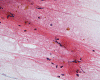

Panel A to E are MR images. Panel F and G are taken from intraoperative cytologic preparation. Panel H to M are taken from frozen section. Panel N and O are from paraffin section. These sections are stained by hematoxylin-eosin stain. Panel P is immunohistochemistry for neurofilament proteins. Panel Q is stained by Luxol fast blue-Periodic acid Schiff (LFB-PAS) stain.

Pathology:

| DIAGNOSIS: Eosinophilic myelitis. |

Pathology of eosinophilic myelitis

Eosinophilic myelitis is featured by lymphocytic infiltration accompanied by a varying intensity of eosinophils. Both the myelin and axons may be damaged. Axonal spheroids can be seen and indicate primary axonal damage rather than secondary damage following demyelination 14, 15. Destruction of axons in the lesion may well explain the relatively poor recovery of this condition. There is increase in eosinophils in CSF in the our under discussion. However, the CSF studies are normal in two previous studies 14, 15.